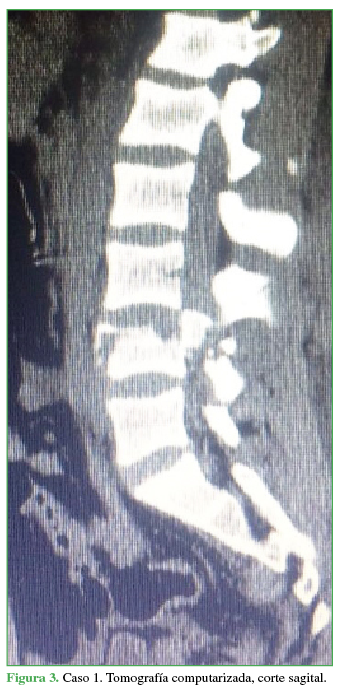

PropiaEl paciente es trasladado al Servicio de Urgencia del hospital regional y, de allí, es derivado a nuestro centro, a través de su obra social. Ingresa, reactivo, lúcido (escala de Glasgow 15/15), con estabilidad hemodinámica y síndrome de cauda equina incompleto (grado B según el puntaje de la ASIA).19 Se solicitan radiografías y TC de columna cervical, torácica y lumbosacra. Se constata fractura vertebral lumbar baja con compromiso de la cuarta vértebra lumbar (L4), de tipo estallido, con retropulsión de un fragmento voluminoso del muro posterior en el canal, con impronta en el saco dural. La resonancia magnética no mostró una lesión del complejo ligamentario posterior, por lo que se interpreta, según la clasificación AO, como L4: A3, N3, M0 (Figuras 2 y 3). Sin deformidad en cifosis significativa y con un colapso vertebral inferior al 50%. Se constata una lesión hepática asociada, se lo somete a una laparotomía de urgencia y queda internado en la Unidad de Terapia Intensiva.

Tomografía computarizada, corte sagital